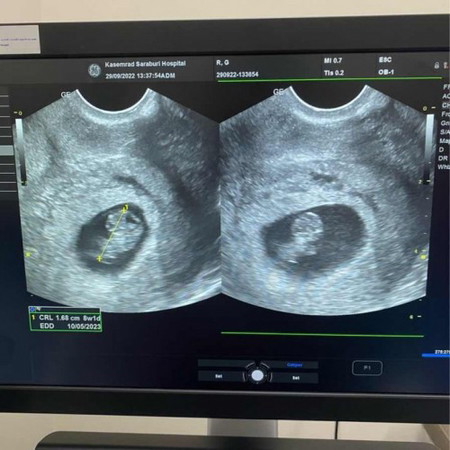

8w1d เจอจิ๋วแล้วว 👶🏻👧🏻🫶🏻 ตอนแรกแม่เคลียดมาก เสี่ยงท้องนอกมดลูก เพราะน้องยังเล็ก บวกกับไปเจอถุงเล็กๆที่ปีกมดลูกอีก 👑 ตอนนี้จิ๋วยอมออกมาเจอแม่แล้ว เกาะพุงแม่แน่นๆนะต้าวว 💜 #ทีมพ.ค66

ของ แม่บ้านนี้ ท้องสองเพิ่งแท้งไป ซาวตอน8สัปดา ไม่เจอ น้อง มาท้องสาม ซาวเจอน้องตั้งแต่ 6สัปดา เลย ค่ะ ดีใจมาก ค่ะ แต่แม่บ้านนี้มีภาวะแท้งคุกคาม ต้องระวัง อย่างดีเลยค่ะ +กะแพ้ท้องหนักมาก ค่ะ ทีม พ.ค 66 เหมือนกันค่ะ